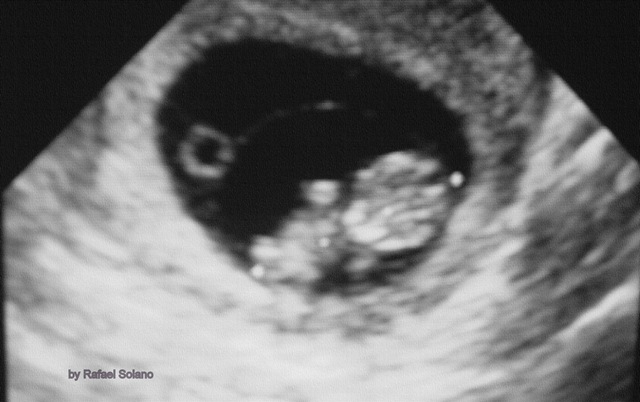

El aborto es la terminación espontánea o intencional del embarazo antes de las 20 semanas. Con frecuencia ocurre durante las primeras 12 semanas de embarazo, y en muchos de los casos la causa es una anomalía cromosómica.

Aborto es la terminación espontánea o intencional del embarazo ante de las 20 semanas. Más del 80% se produce durante las primeras 12 semanas de embarazo, y en más de la mitad de estos abortos tempranos la causa son anomalías cromosómicas.

Existen otras causas y/o factores asociados, donde destacan: infecciones, anomalías endócrinas, tabaquismo, defectos uterinos (miomas) y alteraciones inmunológicas entre la madre y el feto, etcétera.